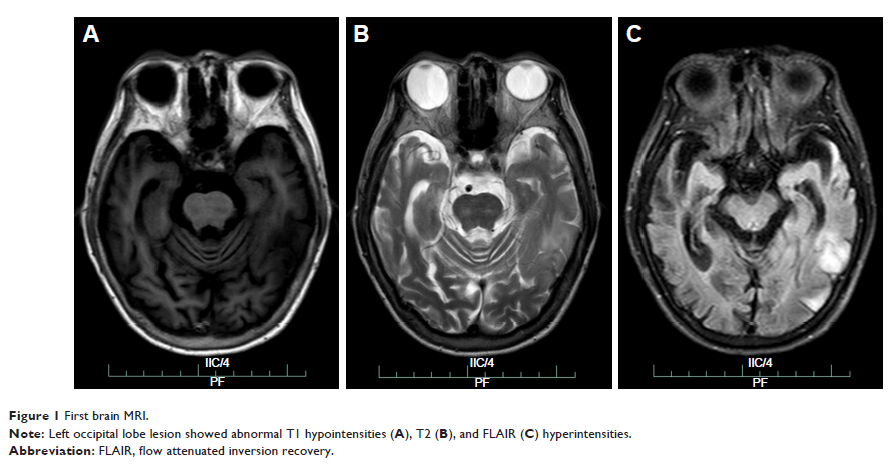

Case Report

- 作者:Gao-Li Fang, Yang Zheng, Yin-Xi Zhang

- 期刊:Clinical Interventions in Aging